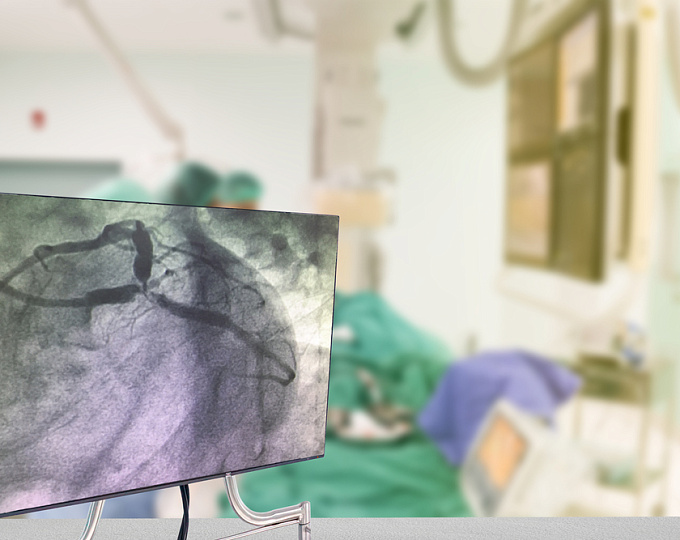

ЧКВ у пациентов с ишемической сердечной недостаточностью: ждать ли улучшения прогноза?

Целесообразность выполнения чрескожного коронарного вмешательства (ЧКВ) у пациентов с ишемической сердечной недостаточностью до конца не определена.

В связи с чем целью рандомизированного исследования REVIVED-BCIS2 была оценка эффективности ЧКВ в улучшении прогноза у пациентов с ишемической сердечной недостаточностью.

Участниками исследования были пациенты с ишемической хронической сердечной недостаточностью (фракция выброса ≤35%), жизнеспособным миокардом и тяжелым поражением коронарных артерий. В соотношении 1:1 они рандомизировались в группы ЧКВ и оптимальной медикаментозной терапии, и только оптимальной медикаментозной терапии.

Первичной конечной точкой была смерть от всех причин и госпитализации по поводу сердечной недостаточности.

• В исследование было включено 700 пациентов. Медиана наблюдения за ними составила 41 месяц. За это время частота наступления событий, включенных в первичную конечную точку, составила 37.2% в группе ЧКВ и 38% в группе контроля (отношение рисков 0.99; 95% доверительный интервал 0.78-1.27).

• Значение фракции выброса левого желудочка было сопоставимым в двух группах как через 6 (средняя разница -1.6 процентный пункт; 95% доверительный интервал -3.7; 0.5), так и через 12 месяцев (средняя разница 0.9; 95% доверительный интервал -1.7; 3.4) месяцев.

• Качество жизни в группе ЧКВ было несколько лучше через 6 и 12 месяцев после его проведения, однако к 24 месяцу эти преимущества нивелировались.

Таким образом, у пациентов с ишемической сердечной недостаточностью выполнение ЧКВ не сопровождается улучшением прогноза. В очередной раз ЧКВ оказалось не лучше оптимальной медикаментозной терапии в неострой ситуации.